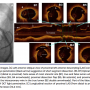

angiography via the left radial artery demonstrated an eccentric, discrete 70% lesion involving the proximal left anterior descending (LAD) artery, at the origin of the first diagonal branch. Linear dye penetration into the vessel wall was noted, suggesting an ulcerated lesion or focal dissection (Figure 1A). The left main artery was noted to be ectatic, but the rest of the coronary anatomy demonstrated minimal luminal irregularities. After crossing the lesion with a standard coronary guidewire, optical coherence tomography (OCT) imaging (C7 Dragonfly catheter; St. Jude Medical) was performed to define morphologic features of the lesion, revealing a focal out-pouching of the vessel with a disrupted edge, consistent with dissection with evidence of residual acute (red) thrombus at the lumen border (Figures 1B and 1C). The vessel at the most stenotic site was noted to consist of mixed fibrotic and lipid plaque with a minimal lumen diameter of 1.99 mm and minimal luminal area of 4.34 mm2. The lumen dimensions by OCT in the region proximal and distal to the dissection were not noted to be aneurysmal, with minimal lumen diameter of 3.24 mm and a minimal lumen area of 8.24 mm2 at the proximal reference segment. The 14.2 mm-long lesion was approached by stenting with a 3.25 x 18 mm everolimus-eluting stent, followed by postdilatation with excellent angiographic results and no evidence of residual dissection (Figure 2B). Post-stent OCT imaging demonstrated no evidence of stent malapposition, and no uncovered dissection flap (Figure 2C). The patient was discharged uneventfully, without further symptoms. Six months later, coronary angiography was repeated as part of an atypical chest pain evaluation demonstrating no evidence of recurrent or residual coronary dissection and a widely patent stent (Figure 2D).

Coronary artery dissection leads to formation of a false lumen, which may cause arterial lumen compromise, particularly if there is hematoma formation. Routine angiographic assessment in such situations is marked by significant false-positive and false-negative results. This poses unique challenges during percutaneous coronary intervention (PCI), where identification of the true arterial lumen or proper intracoronary guidewire placement is crucial. OCT provides high-resolution intraluminal images, and therefore can aid in diagnosis and guide management strategies in such cases. In our patient, OCT was valuable in establishing the diagnosis of coronary dissection by visualization of the dissection flap and excluding an aneurysm or ulceration. In addition, OCT demonstrated the exact location and arc of disrupted intimal layers, allowed differentiation of true and false lumen, and verified optimal placement of the intracoronary wire in the true lumen. Successful outcome of a PCI for dissection requires accurate assessment of lesion dimensions for optimal stent sizing, successful sealing of the subintimal entry site, and in some cases covering the entire dissected segment. Furthermore, OCT imaging of our patient aided in explaining the mechanism of coronary ischemia in the setting of a non-obstructive plaque by demonstrating vessel disruption, dissection, and the presence of residual thrombus.